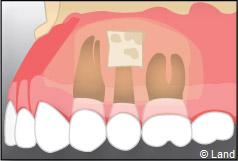

Une préparation de l’extrémité restante est effectuée à l’aide d’une petite fraise boule, de façon à recevoir une obturation canalaire étanche.

Un biomatériau et une membrane destinée à la régénération osseuse guidée peuvent être mis en place dans la cavité ainsi dégagée.